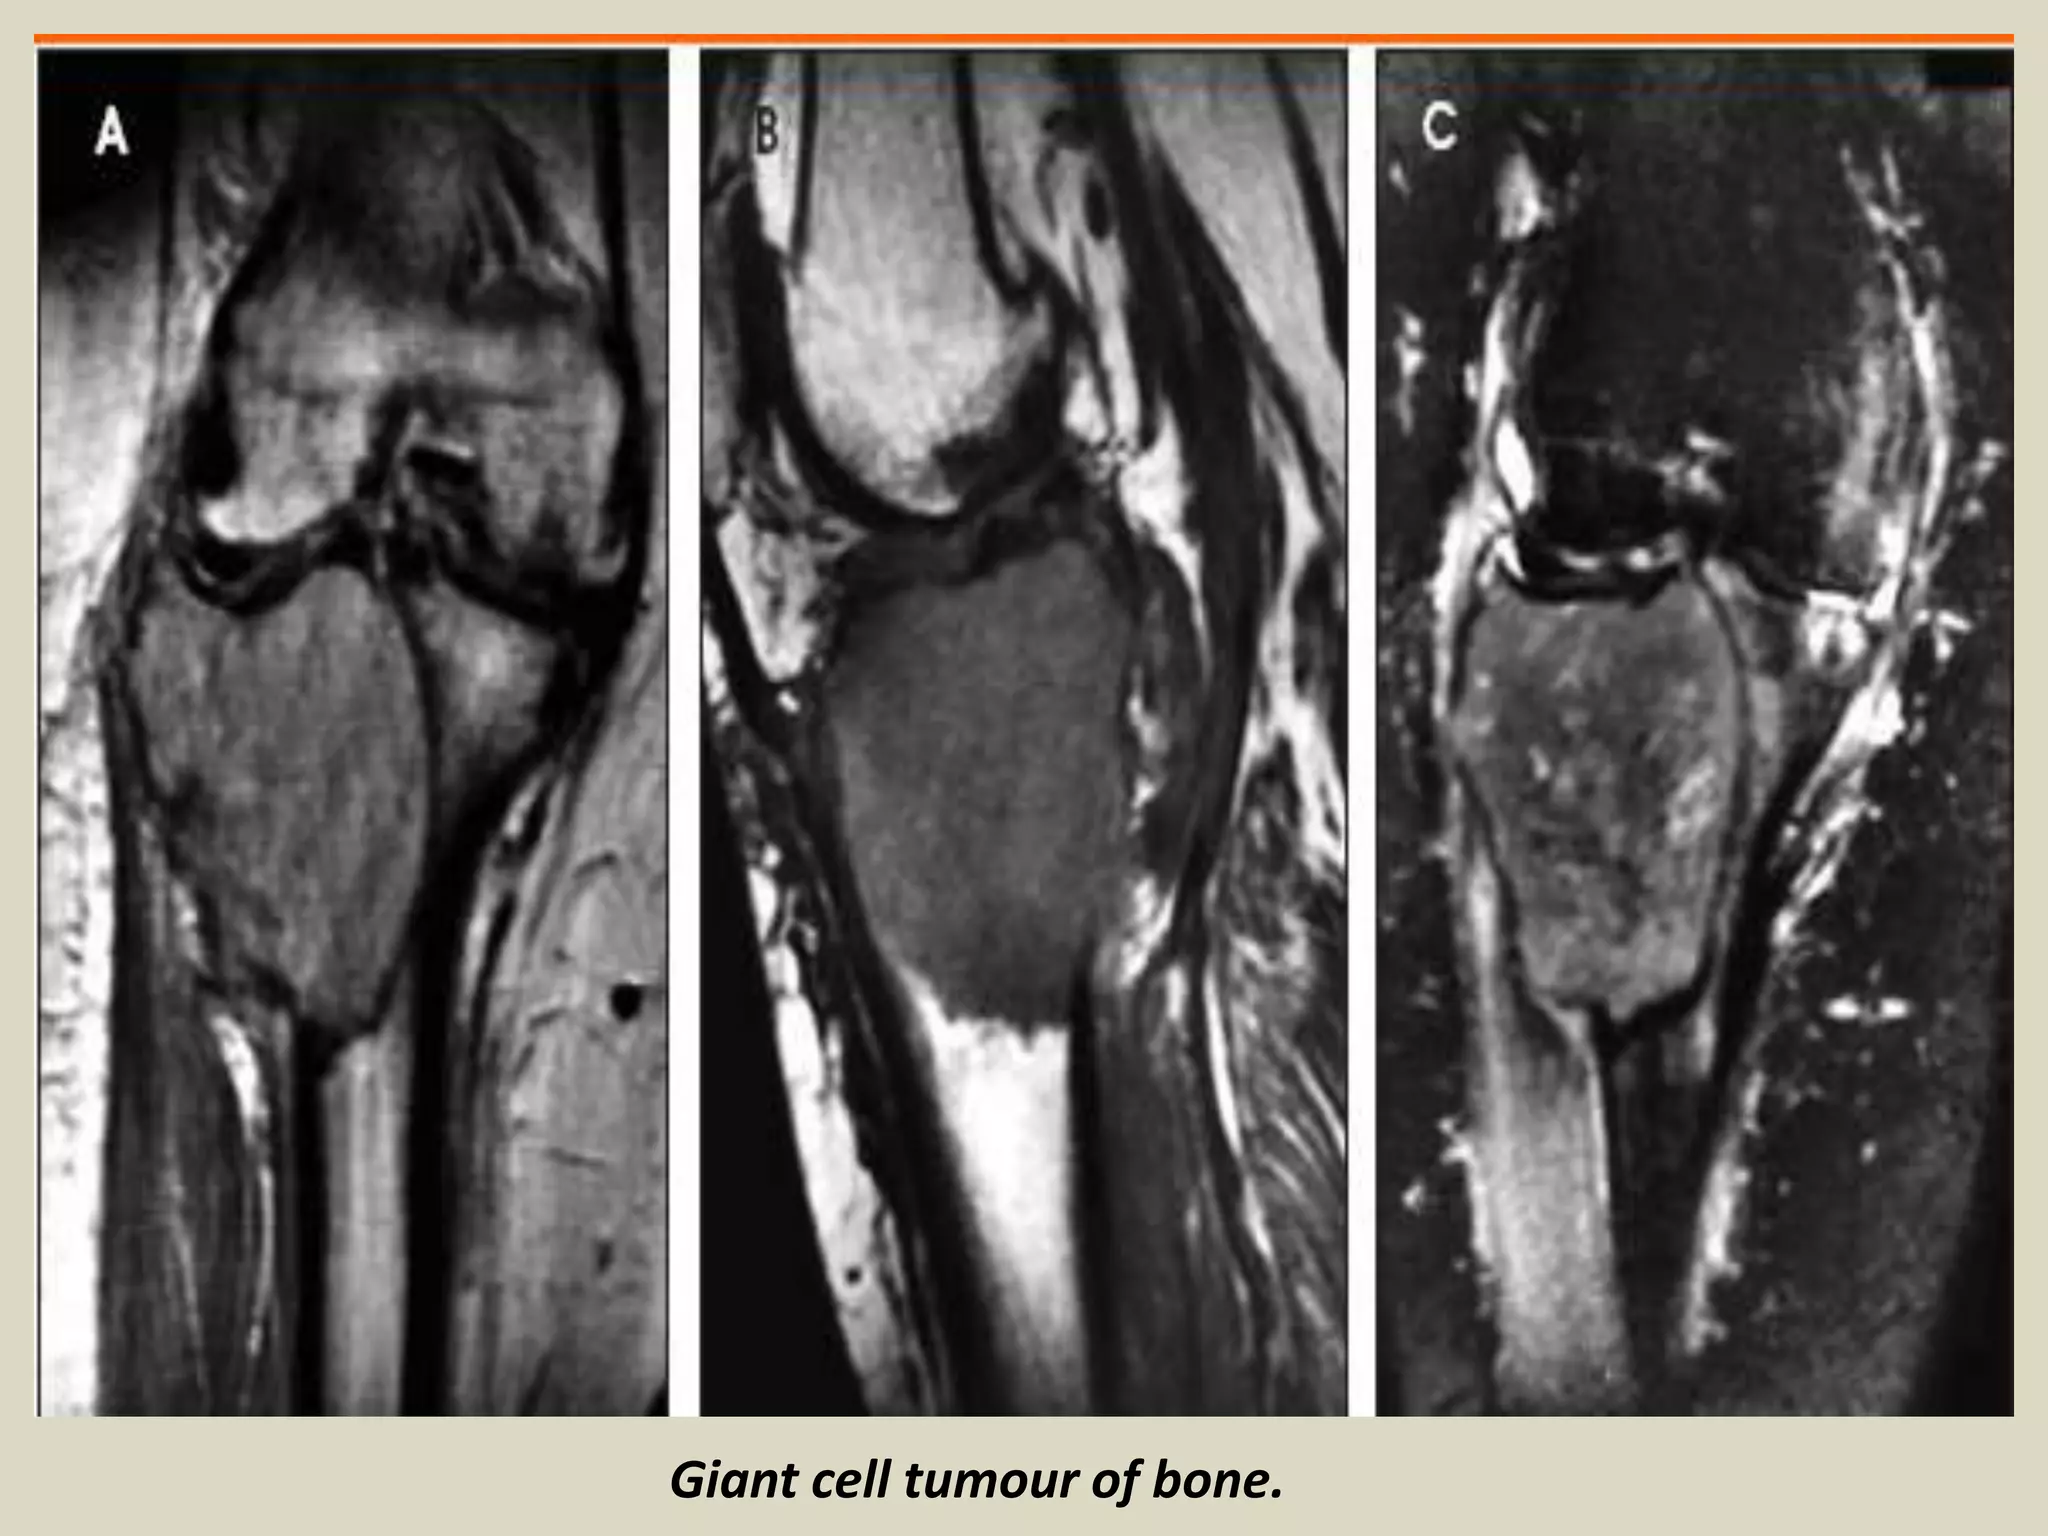

GIANT CELL TUMOR

Definition: Benign, locally aggressive neoplasm.

- Composed of sheets of neoplastic ovoid mononuclear cells interspersed with

uniformly distributed large, osteoclast like giant cells.

Epidemiology:

- Giant cell tumour represents around 4-5% of all primary bone tumours.

- Peak incidence is between the ages of 20 and 45.

- 10-15% of cases occur in the second decade.

- Not commonly seen in adolescents, although cases were described.

- There is slight female predominance described.

Sites of involvement:

- Giant cell tumours typically affect the ends of long bones, especially the distal femur, proximal tibia, distal

radius and proximal humerus.

- About 5% affect flat bones, especially those of the pelvis.

- Multicenteric giant cell tumors are very rare and tend to involve the small bones of the distal extremities.

Clinical findings:

- Patients typically present with pain, swelling and often limitation of joint movement

- Pathological fracture is seen in 5-10% of patients.

Imaging:

- X-rays of lesions in long bones usually show an expanding and eccentric area of lysis.

- Lesion normally involves the epiphysis and adjacent metaphysis.

- Extension up to the subchondral plate, sometimes with joint involvement may be present.

- Rarely, the tumour is confined to the metaphysis, usually in adolescents where the tumour lies in relation

to an open growth plate, but occasionally also in older adults.

- Diaphyseal lesions are exceptional.

- CT scanning gives a more accurate assessment of cortical thinning and penetration than plain radiographs.

Giant cell tumour of bone.